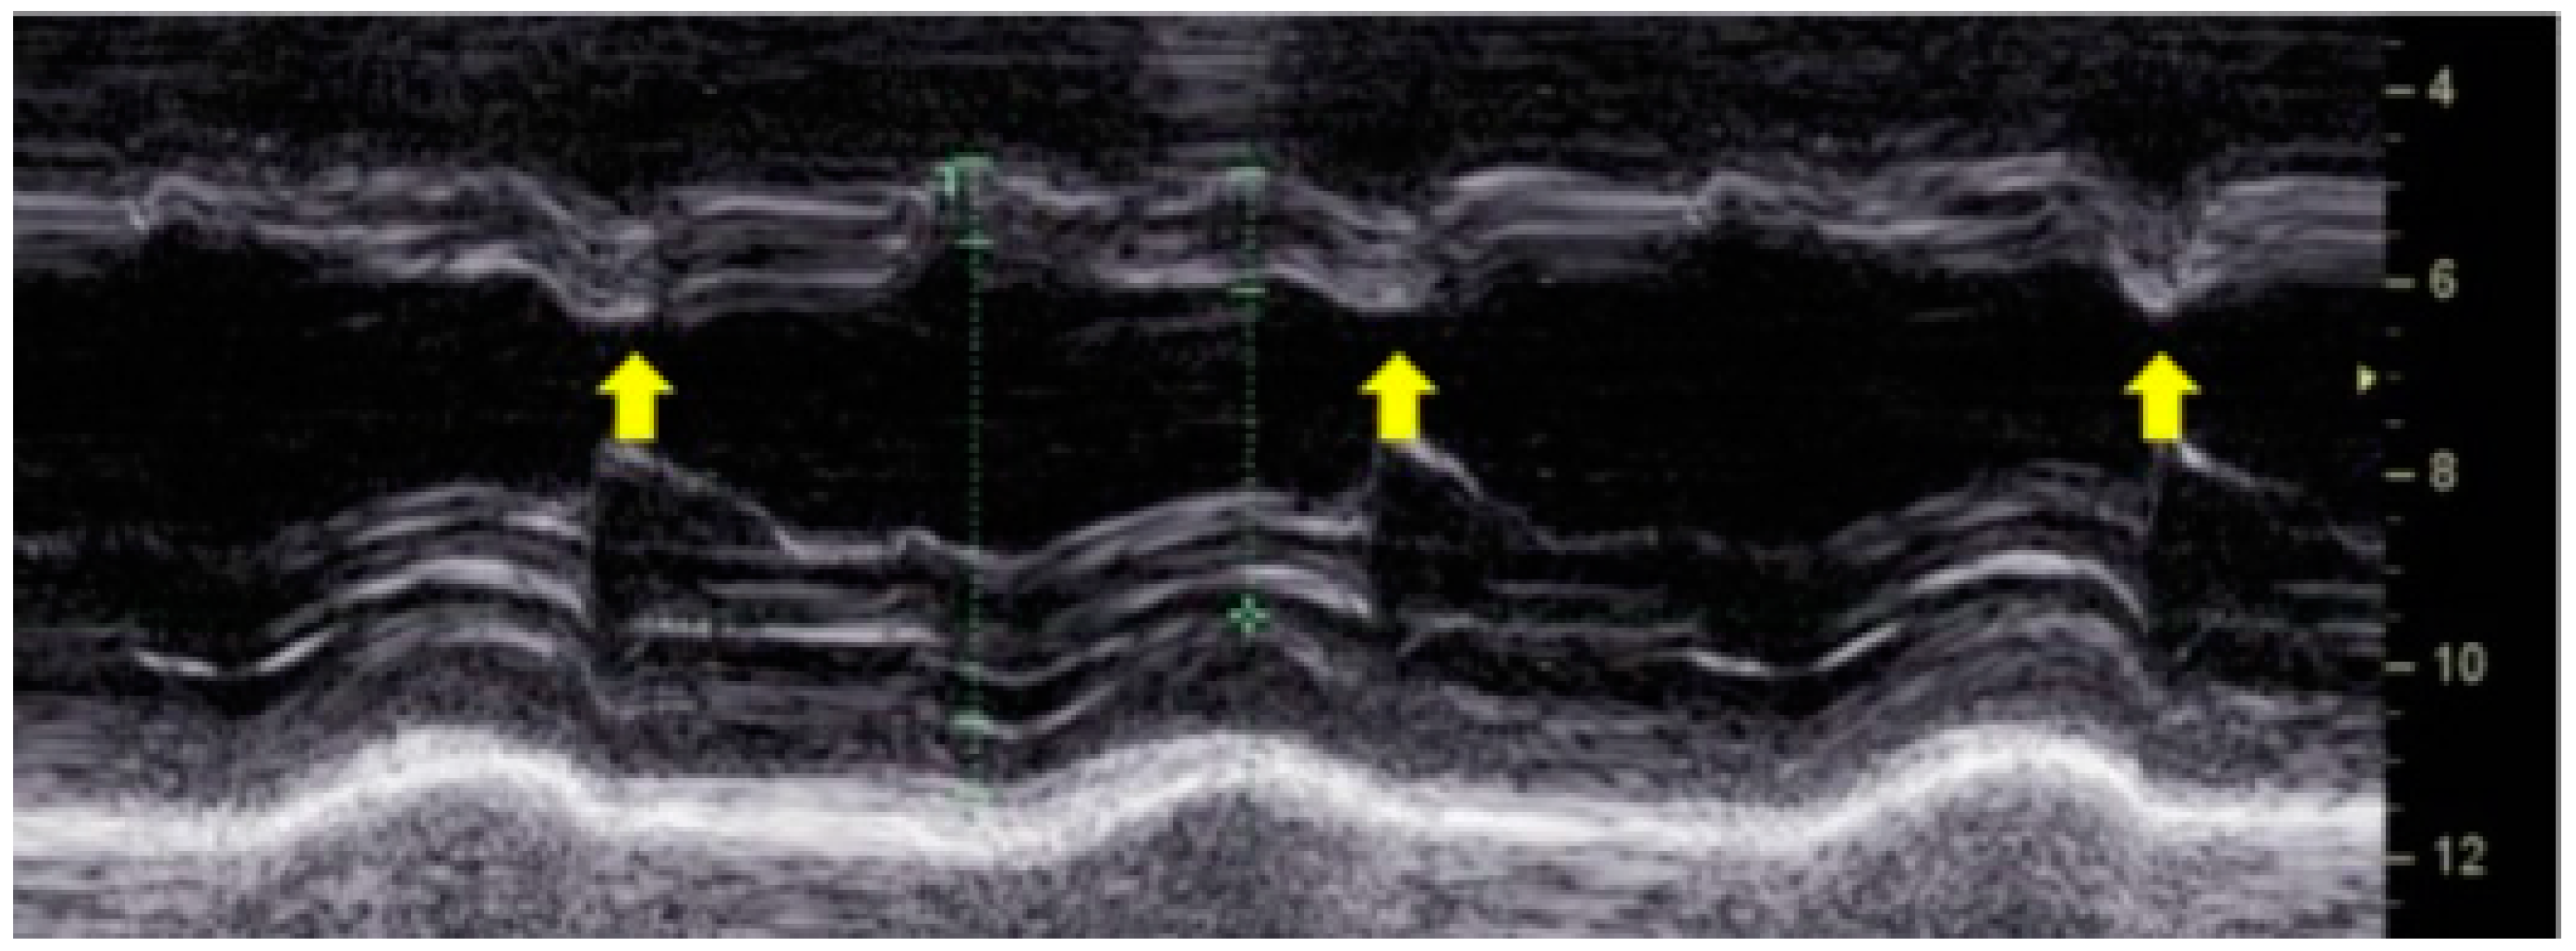

A hallmark feature of LBBB-induced dyssynchrony is paradoxical septal motion. Early contraction of the right ventricle pulls the septum toward the left ventricle, while the delayed lateral wall contraction stretches the septum back toward the right ventricle. This phenomenon, known as "septal flash", is a key echocardiographic finding associated with inefficient myocardial contraction [11] (Figure 3). The resulting uncoordinated motion increases myocardial wall stress and reduces left ventricular ejection efficiency, leading to progressive systolic dysfunction.

Figure 3. M-mode echocardiography showing septal flash, a characteristic sign of left bundle branch block. The yellow arrows indicate the early systolic septal motion abnormality caused by dyssynchronous ventricular activation.